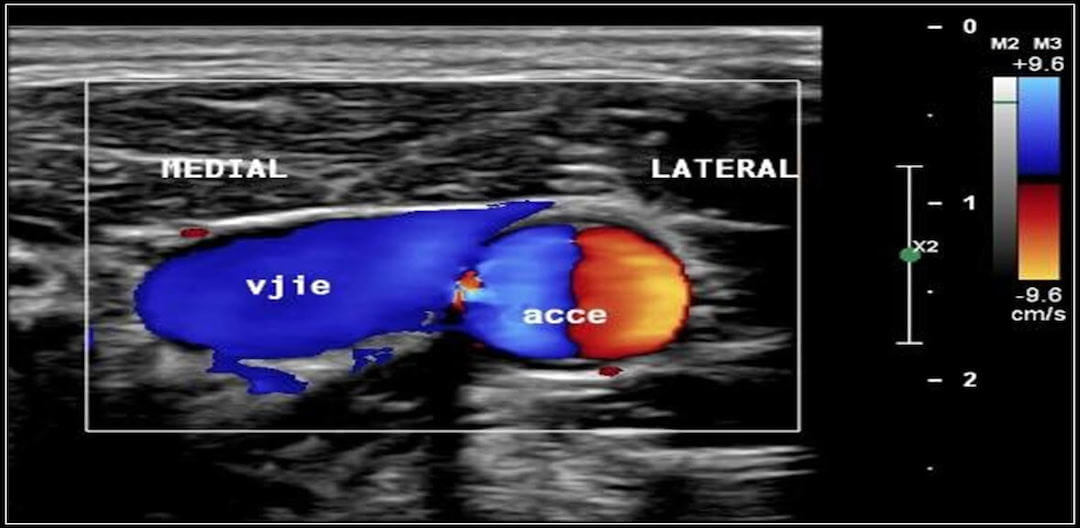

Punção venosa guiada por ultrassom versus punção direta na colocação de uma via venosa central